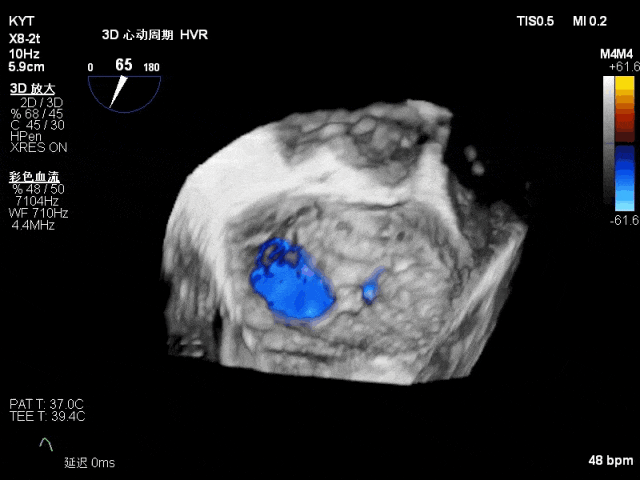

TEE 3D示二尖瓣内交界区脱垂及断裂腱索

二尖瓣PC区收缩期脱向左房侧,其上可见飘带样回声。二尖瓣口左房侧见大量反流信号,主要呈偏心性并沿前叶走行达房顶并折返。